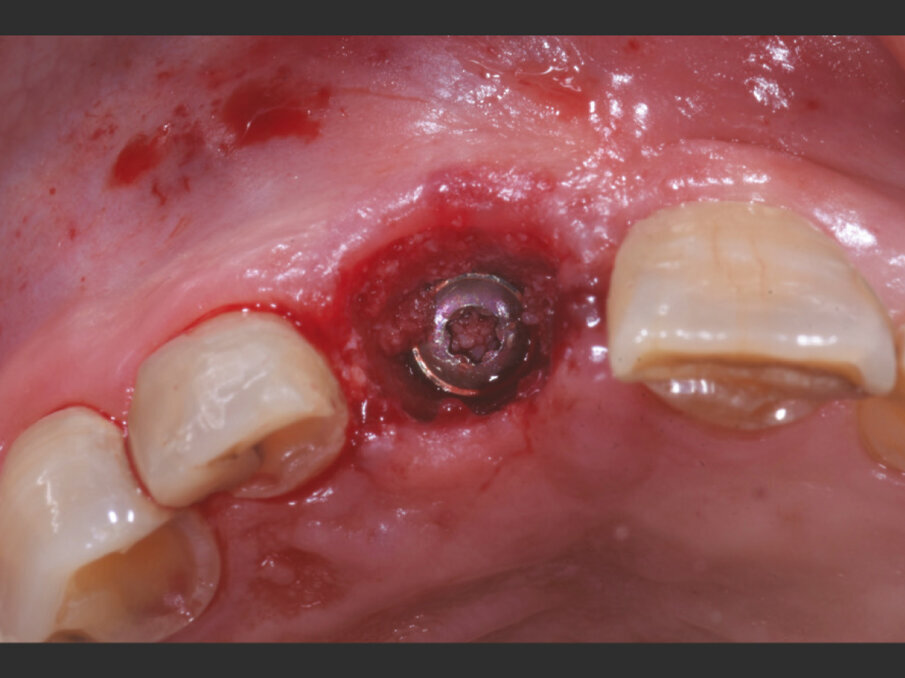

Il giorno dell’intervento, dopo somministrazione locale di articaina al 4% e adrenalina 1:100.000, l’elemento viene lussato delicatamente mantenendo integri i tessuti molli tramite l’uso di periotomi dedicati (Carda #2 e Carda #3 - Omnia) ed estratto. L’alveolo viene curettato e deterso con soluzione salina, e il tessuto epiteliale sulculare viene rimosso con una lama 15c, così da esporre il sottostante tessuto connettivale. Viene preparata un’osteotomia calibrata con frese dedicate, così da ingaggiare l’apice implantare (BLT Bone Level Tapered Roxolid SLActive, Straumann 4.1x14 mm) nel triangolo osseo apicale e palatale all’apice alveolare e posizionare il profilo coronale dell’impianto 1 mm al di sotto del margine della cresta vestibolare. Dopo il posizionamento implantare, con l’ausilio di un compattatore d’osso conico (Carda #4 - Omnia), il gap residuo vestibolare viene colmato con osso bovino deproteinizzato (Geistlich Bio-oss Collagen 50 mg, Geistlich) così da assicurare un perfetto riempimento tridimensionale dell’alveolo residuo. L’impianto viene infine posizionato con un torque di 50 N/cm (Figg. 3, 4a, 4b).

Fig. 3 - Straumann BLT Roxolid SLActive RC 4.1 x 14 mm.

Fig. 4a - Impianto inserito lontano dalla corticale ossea vestibolare in modo da creare un gap superiore a 2 mm.

Fig. 4b - Il jumping space tra impianto e corticale ossee viene colmato con Geistlich BioOss Collagen.